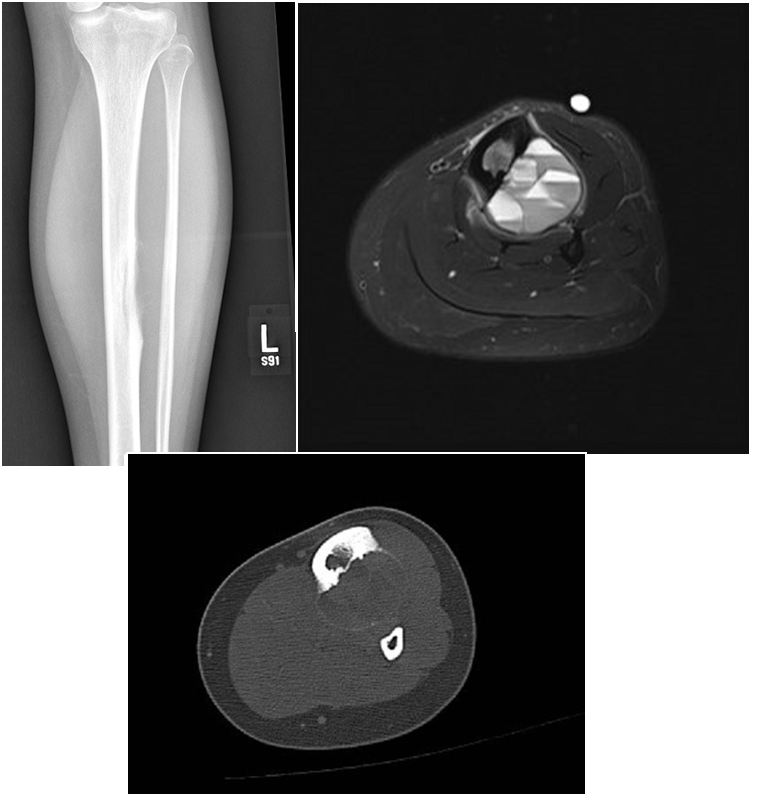

A 79-year old female presents with complaints of right hip pain for 2 months. She denies prior injury or precipitating event. The pain is made worse by lying on the affected side and occasionally hurts with hip motion. The pain is improved with NSAIDS and placing ice on the lateral aspect of her hip. Her primary care physician ordered x-rays which showed a bone lesion in the proximal femur. Her PCP was concerned she had bone cancer and ordered an MRI of the thigh to further evaluate. AP x-ray and a coronal MRI image are shown above. The patient denies a history of weight loss, fatigue, and history of cancer. On exam the patient has no pain with passive range of motion of the hip in all planes. She has pain with palpation over the greater trochanteric bursae. Motor and sensation are intact throughout the lower extremities. What is the most likely cause of this patient’s pain?